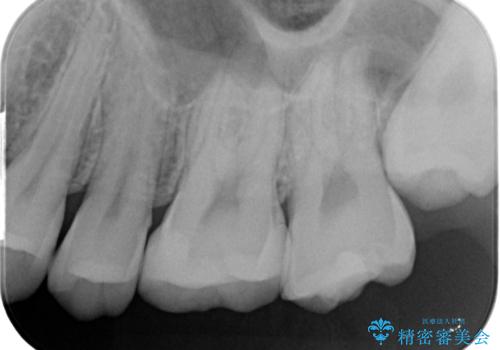

- 歯と歯の間に虫歯(コンタクトカリエス)が見られたので拡大鏡下で取り除き、e-maxインレーで治療を行いました。

歯と歯の間は歯ブラシでは磨けないので毎日フロスや歯間ブラシを使用する事が虫歯になるリスクを下げる事があります。